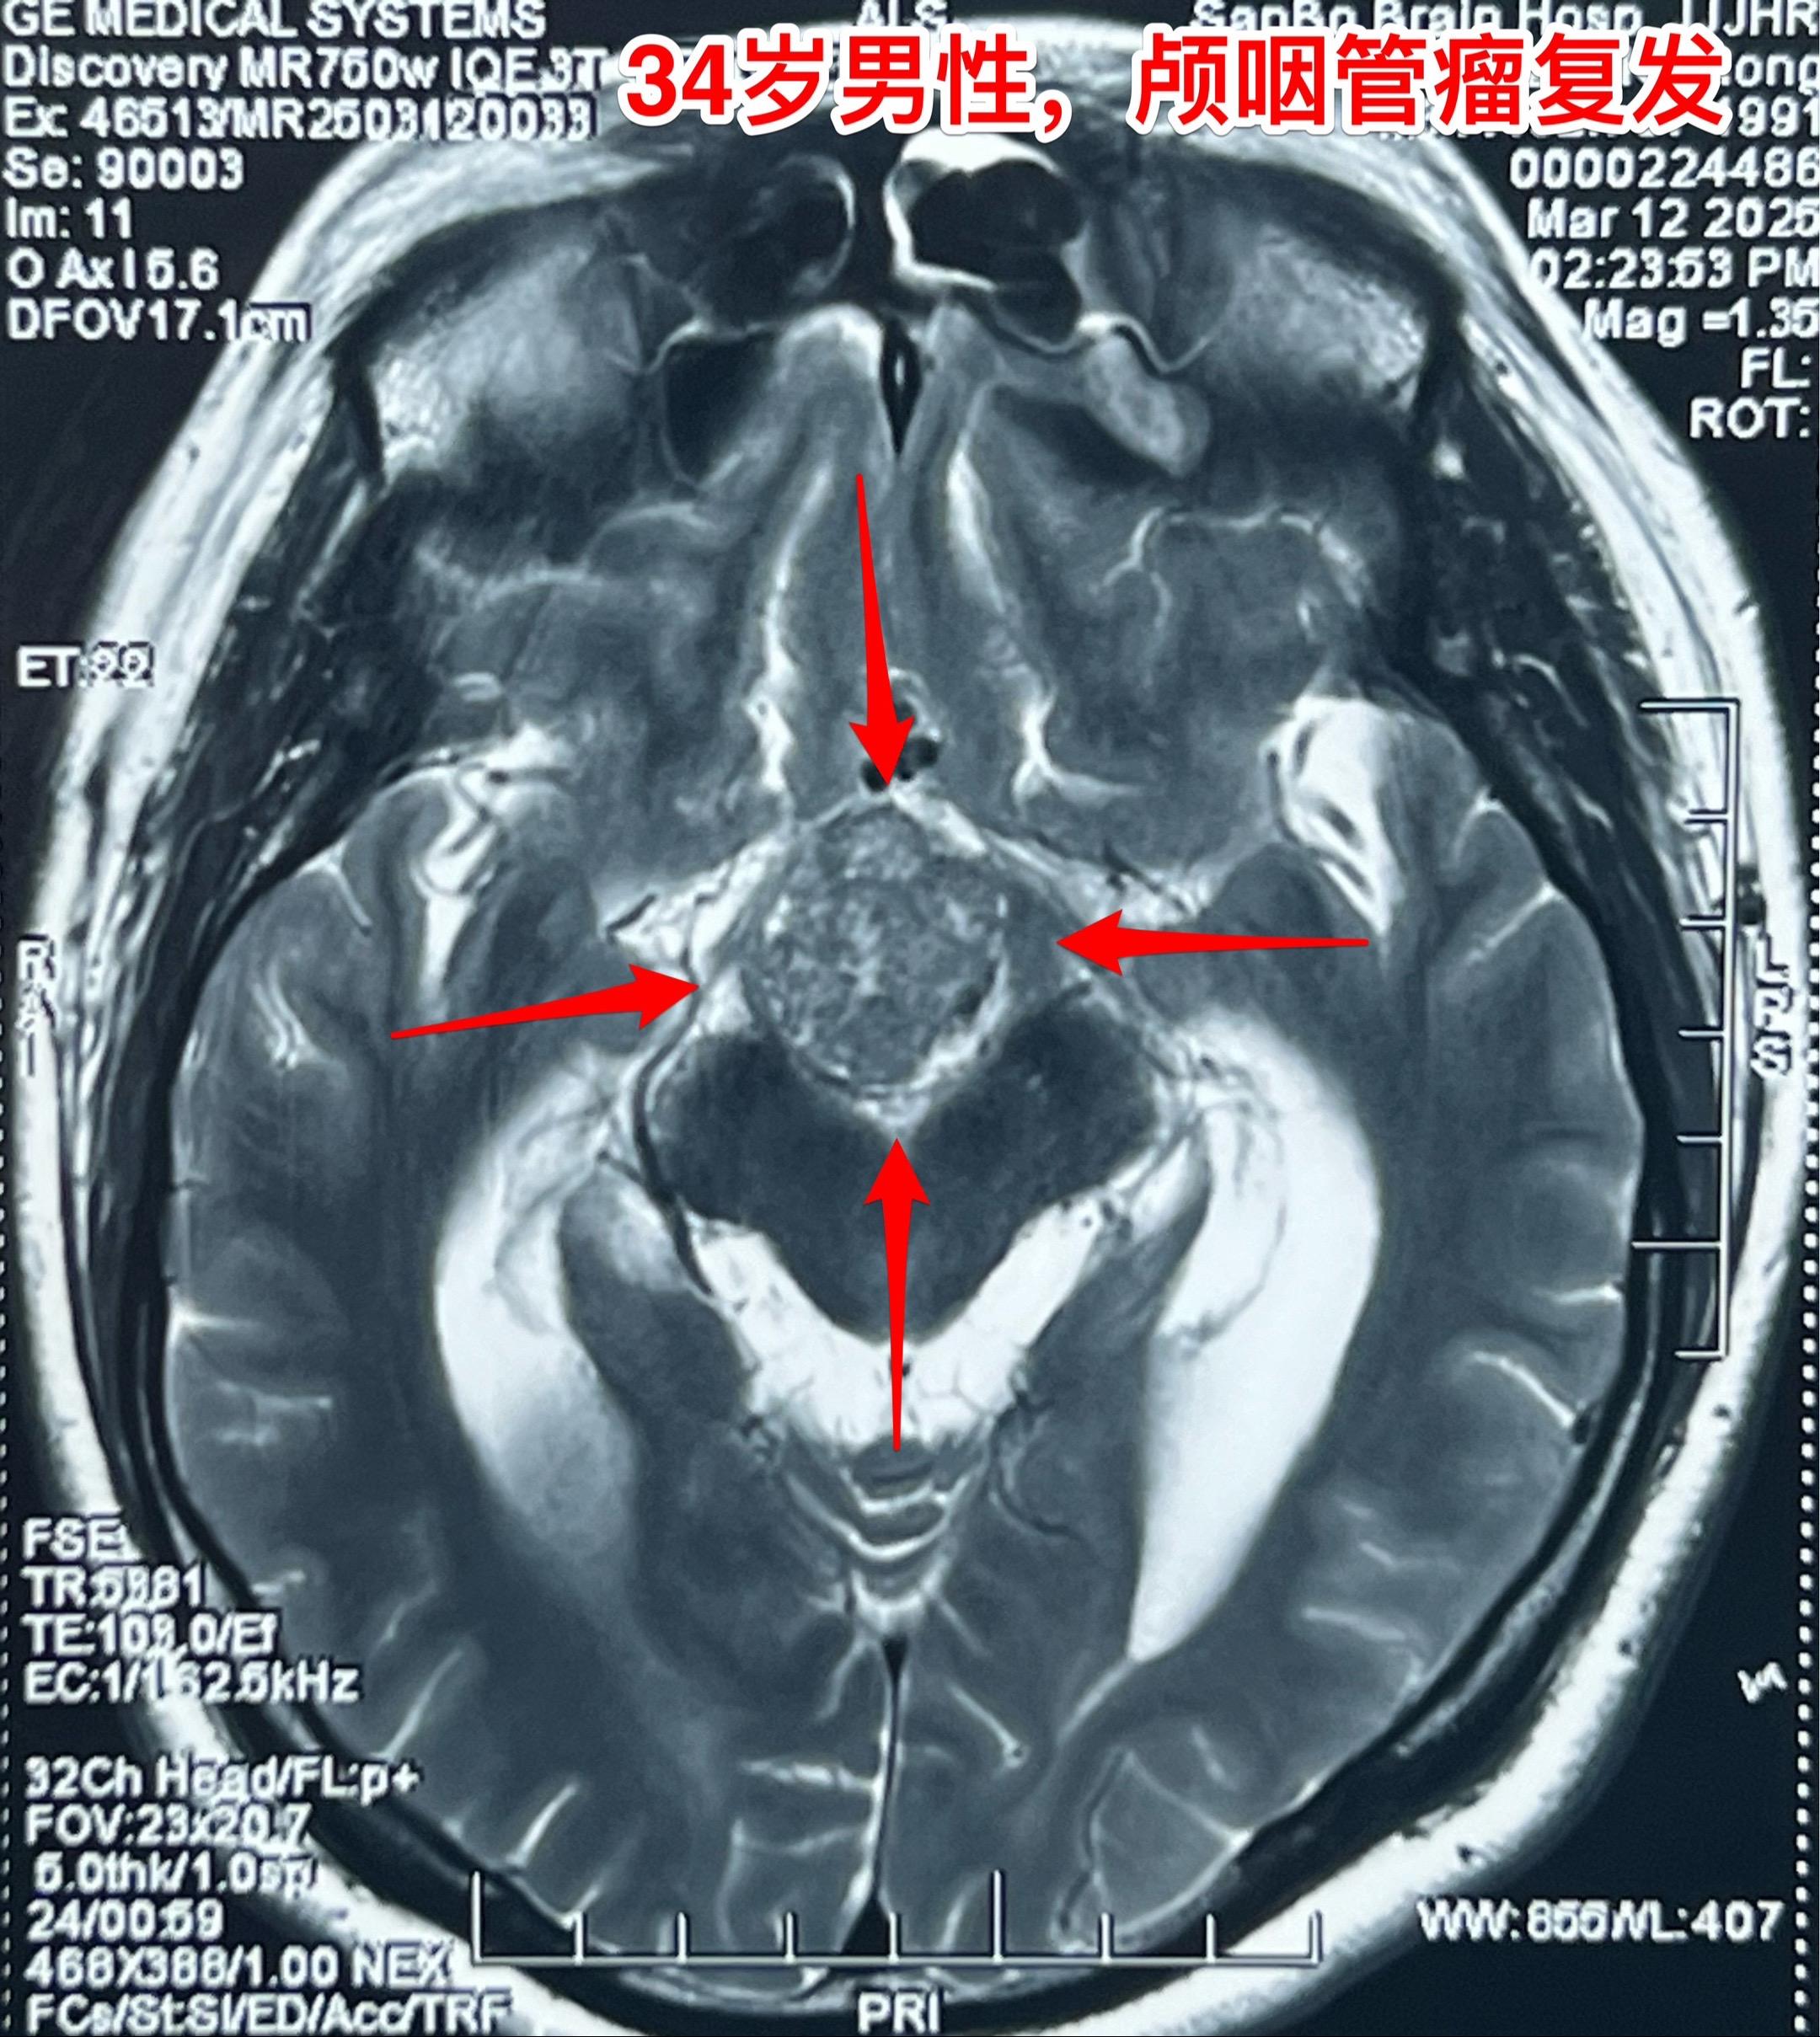

乳头型和造釉型颅咽管瘤的混合型存在吗?34岁男性,广东省惠州市人。一年前因视力下降发现颅咽管瘤,在广东省某医院行开颅手术切除一部分肿瘤。肿瘤复发了来三博脑科医院找我治疗。 第一次手术后病理报告考虑是乳头型颅咽管瘤和造釉型颅咽管瘤的混合型(太罕见了)。手术中还留置了一个动脉瘤夹子、一个Ommaya囊。 昨日作了开颅手术,术中看见肿瘤血供十分丰富,和第三脑室壁及大脑后动脉粘连。手术经历9.5个小时,肿瘤得到完全切除。术后病人的精神状态及四肢活动均很好。希望以后肿瘤不复发。等待病理